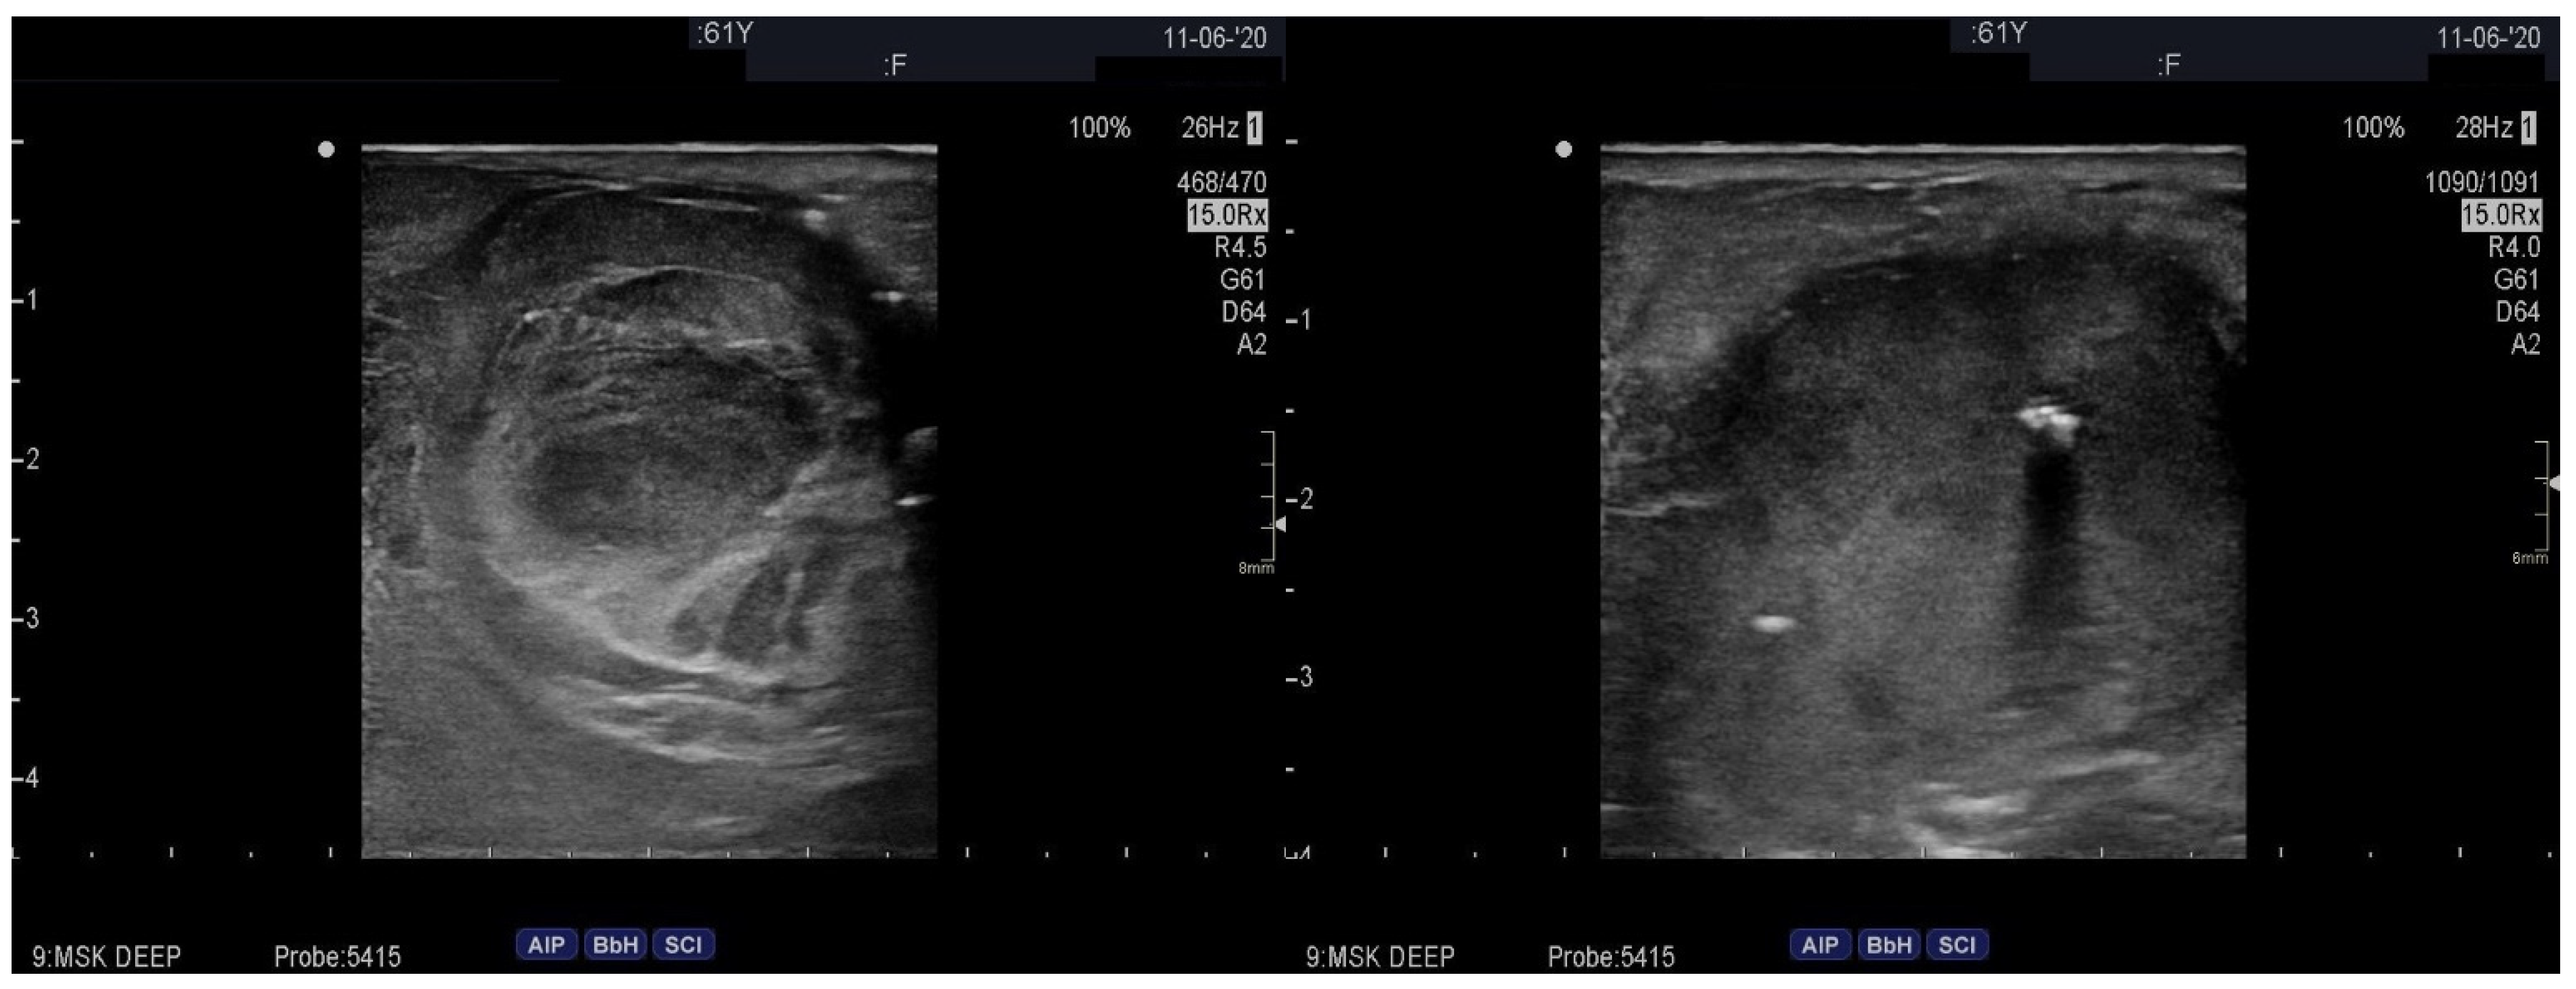

2. Case Presentation